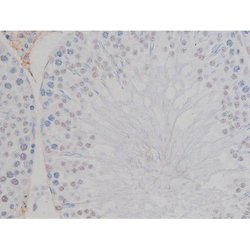

Invitrogen™ Phospho-NPM1 (Thr199) Polyclonal Antibody

Antibody detects endogenous levels of Nucleophosmin only when phosphorylated at Threonine 199.

| Applications | Immunohistochemistry (Paraffin), Western Blot, Immunocytochemistry |